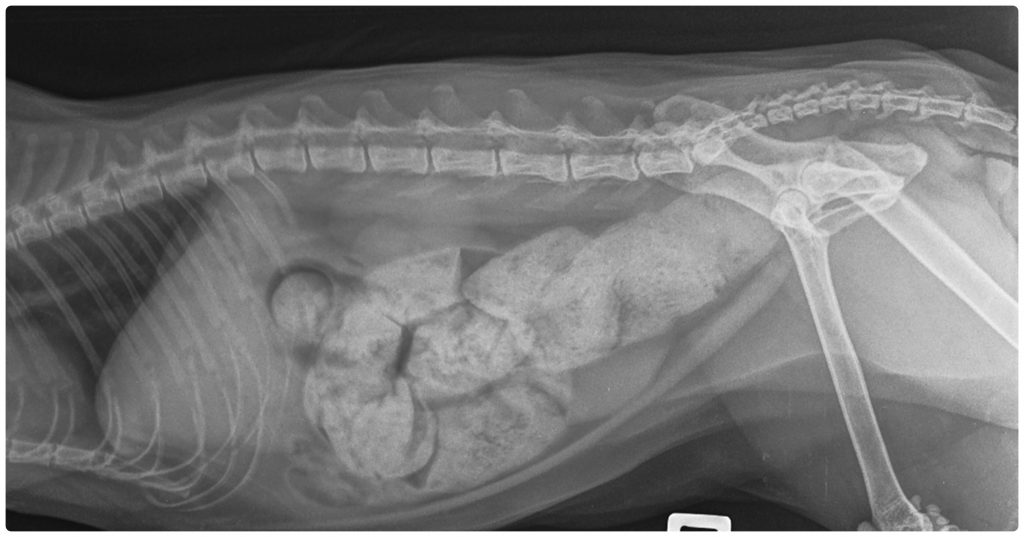

Das Megakolon ist die schwerste Verlaufsform chronischer Verstopfung. Dabei weitet sich der Dickdarm durch wiederholte Überdehnung dauerhaft aus und verliert seine Fähigkeit, den Kot weiterzubefördern. Einige Katzen entwickeln ein Megakolon nach jahrelanger, unbehandelter Verstopfung, andere aufgrund von Beckenverletzungen oder angeborenen Nervendefekten. In einem erheblichen Teil der Fälle lässt sich keine eindeutige Ursache feststellen – man spricht dann von einem idiopathischen Megakolon. Die Diagnose erfolgt in der Regel mittels Röntgenaufnahmen, die eine charakteristische Ausdehnung des Kolons zeigen. Da es sich um eine chronische Erkrankung handelt, ist eine dauerhafte tierärztliche Betreuung notwendig